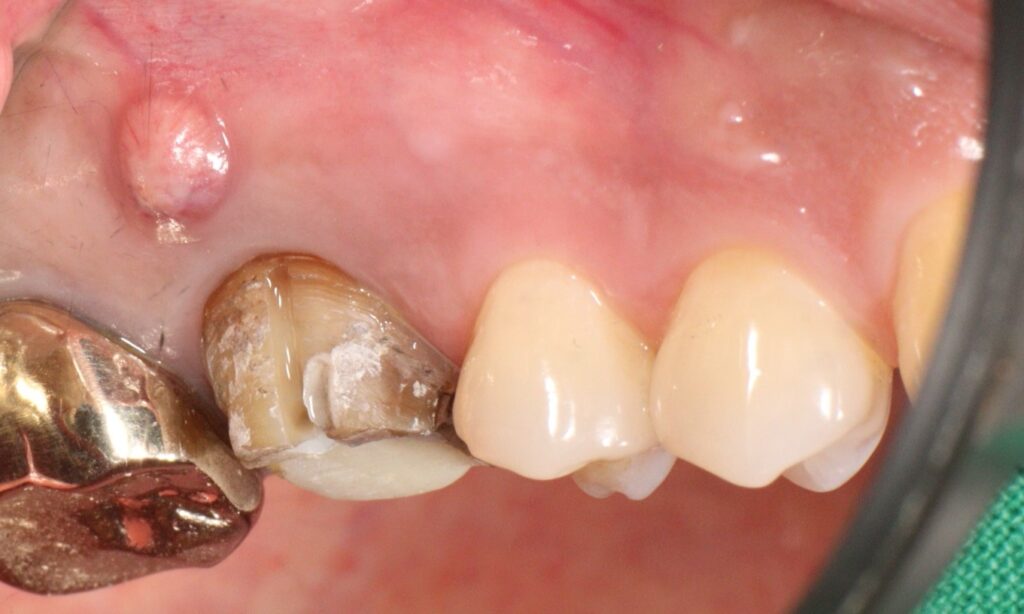

환자분께서는 오른쪽 위 크라운을 씌운

어금니에 염증과 통증이 생겨 치아가

흔들리신다며 광화문치과에 내원해 주셨는데요.

오른쪽 위 첫번째 어금니 치아 뿌리 염증으로 인해

잇몸이 부어 고름 주머니가 형성된 것을

확인할 수 있었는데요.

남아 있는 치질의 양이 적고

예후가 좋지 않을 수 있지만

임플란트 식립을 염두에 두고

기존의 크라운을 제거해보기로 하였습니다.